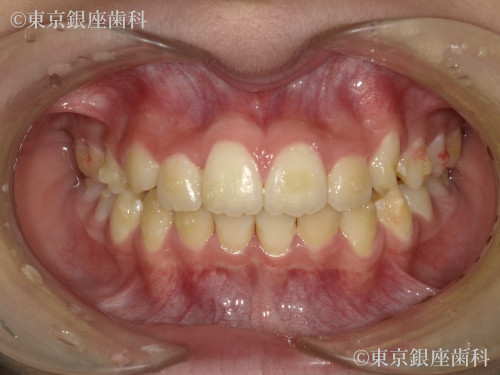

Before

10代 女性

疾患 矯正

施術内容 矯正

治療期間 11ヶ月 費用 65万円(税込)

インビザライン:ファースト